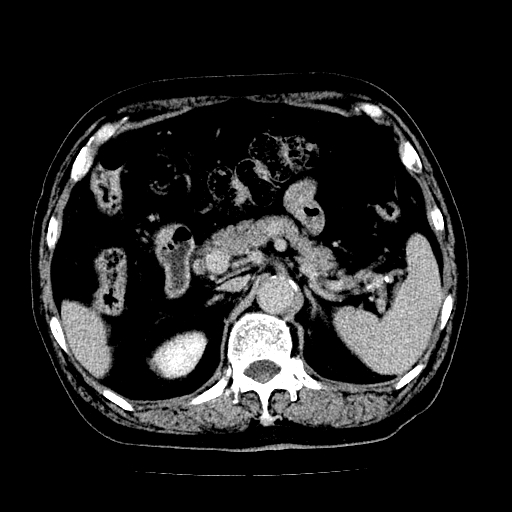

男,71岁,皮肤黄染四天。

肝内外胆管及胆总管上段扩张,考虑为梗阻所致,建议mrcp检查。

胰腺上端胆总管内见软组织影,强化不明显,结合临床,还是考虑低位梗阻性黄疸,胆总管癌可能性大